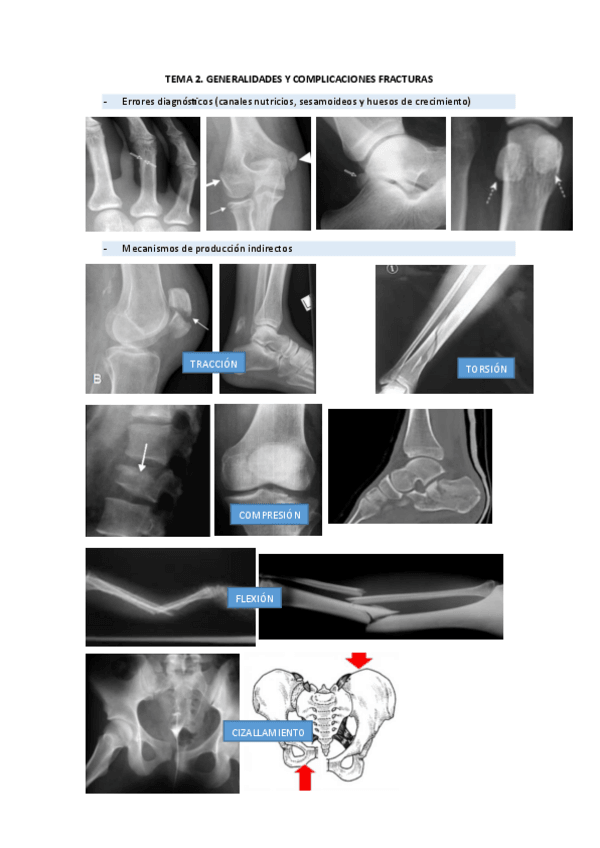

Apuntes - tema-2.-fracturas.pdf